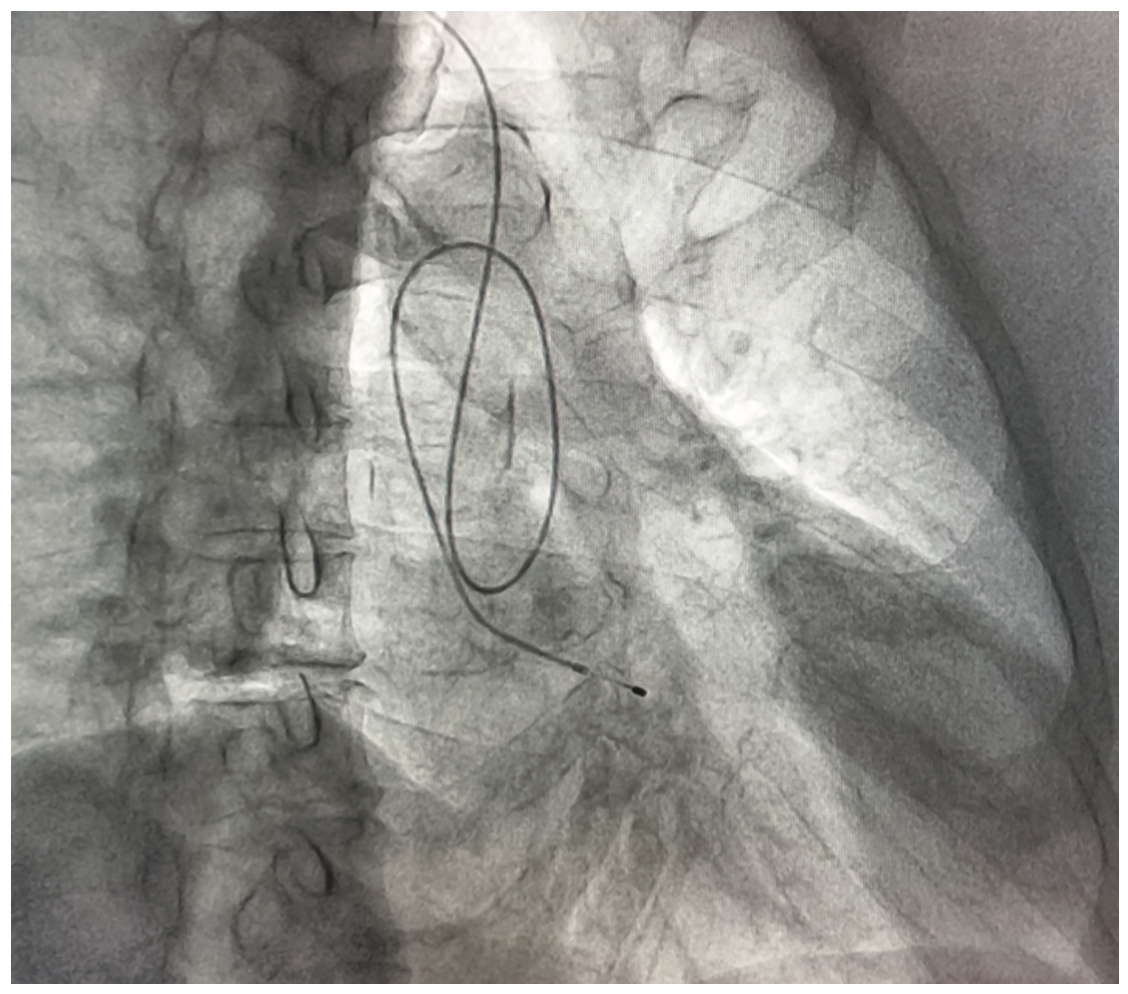

We report the case of a 77-year-old male who underwent temporary pacemaker lead implantation after a symptomatic 2:1 Mobitz type II second-degree block and left bundle branch block conduction (Figure 1). The temporary pacemaker was implanted apparently through the right jugular vein without fluoroscopic guidance, only by monitor guidance. After medical stabilization the patient was referred to our tertiary care center for further management. A cardiovascular system examination was unremarkable. Electrocardiogram showed a paced left bundle branch block pattern; however, with a high threshold stimulation level. The x-ray showed an abnormal lead path (Figure 2). A computed tomography angiography was performed that documented an intra-arterial lead with entry into the right common carotid artery and with the tip crossing the aortic valve and ending in the left ventricular outflow tract (Figure 3). Removal of the lead and relocation of the temporary pacemaker was requested by interventional cardiology. The fluoroscopy showed a temporary pacemaker lead with an arterial course with a loop in the ascending aorta and the tip crossing the aortic valve (Figure 4). A puncture of the right common femoral vein was performed, and a 6 French introducer sheath was placed. The temporary pacemaker lead was advanced to the right ventricle (Figure 5). The intra-arterial lead was removed and an angiogram was performed through the introducer sheath, confirming the arterial site (Figure 6). The introducer sheath was subsequently removed without complications.

Early recognition required careful reading of the 12-lead surface electrocardiogram pacing morphology and other imaging modalities, including chest x-ray, computed tomography, and fluoroscopic images.